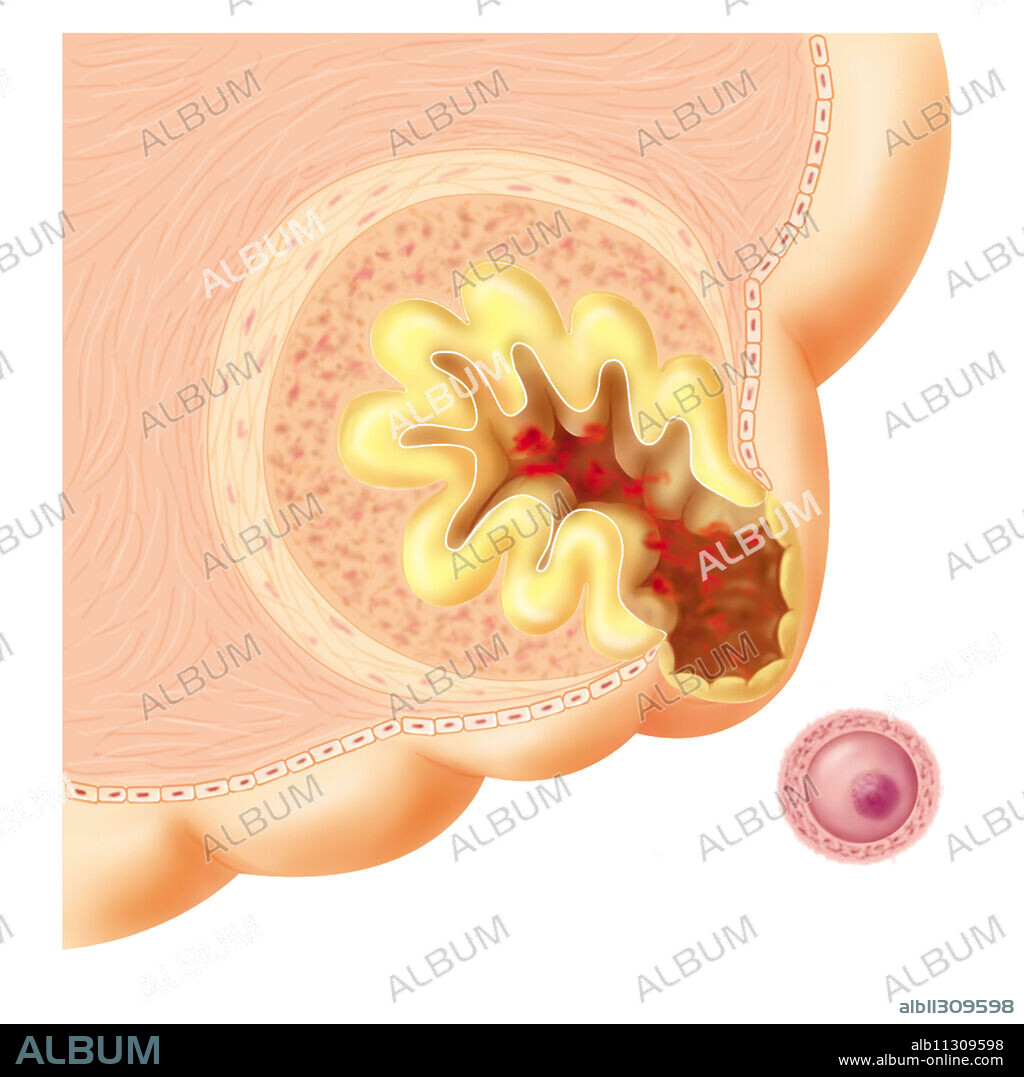

Ovulation, drawing

Ovulation, drawing

Rupture of the ovarian wall and release of the ovum (ovulation) that was in the Graafian follicle.

ARTWORK • CELL • EMBRYOLOGY • FEMALE GAMETE • FEMALE GENITAL ORGANS • FOLLICLE • GAMETE • GENITAL SYSTEM • GERMINAL CELL • GRAAFIAN FOLLICLE • GYN • GYNAECOLOGY • GYNECOLOGY • MEDICINE • MENSTRUAL CYCLE • NORMAL • OOCYTE • OVARIAN CYCLE • OVARIAN FOLLICLE • OVARIAN • OVARY • OVOGENESIS • OVULATION • OVUM • PLAIN BACKGROUND • REPRODUCTIVE SYSTEM • SEXUAL REPRODUCTION • TERTIARY FOLLICLE • ZONA PELLUCIDA